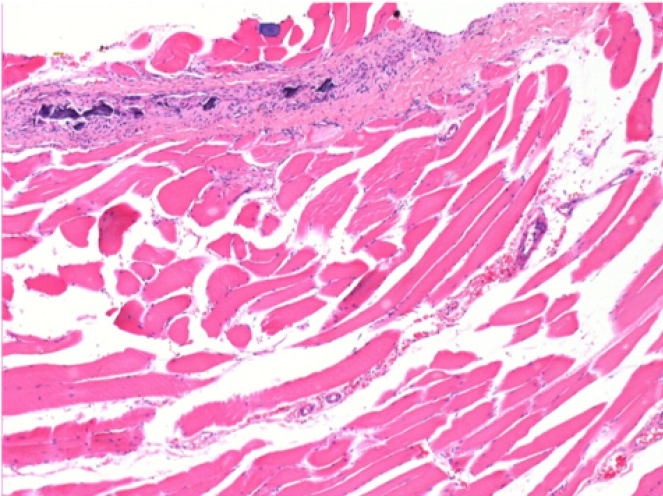

10 días después de la inyección de Endopeel 0,1 ml en el músculo pretibial derecho.

Aquí puede ver la formación de las vacuolas que están rodeadas de linfocitos. Las vacuolas son diferentes a la necrosis tisular. La presencia de linfocitos está relacionada con la permeabilidad de las membranas celulares.

07